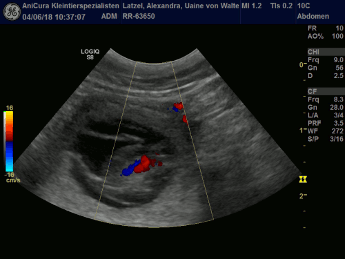

| 04.06.2018 |

Tessa und Uaine sind schwanger! Die Ultraschallbilder beweisen es! Hier die Bilder!!! |

| Hier die Ultraschallbilder von Uaine von Waltenweiler!!! |